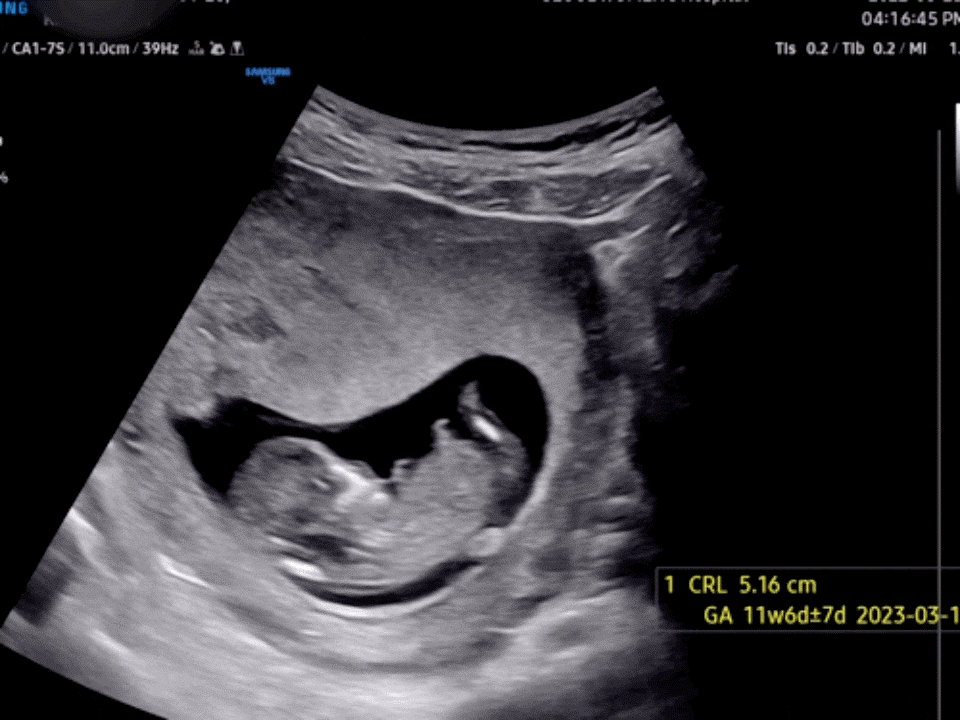

CRL(키): 5.16 나무 투명대 길이: 0.9mm 나무 투명대 길이는 기형아 선별에 중요한 자료이다.2.5~3.0mm 이하가 정상 범위이다.장식은 매우 얇아 지극히 정상적인 것으로 알려졌다.

오늘 본 장식 자료로 정확하게 출산 예정일을 정해줬어.생리일 기준 3.7일이었지만 아기 크기 기준 3.10일로 날짜가 변경됐다.